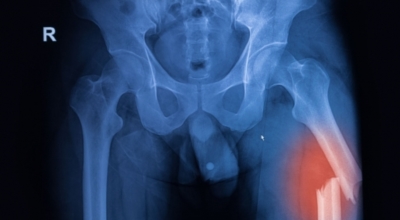

6. 콘드로이친 효능 - 골관절염

콘드로이친은 보통은 골관절염 증상 관리를 위한 치료제로 사용되고 있어요. 미국에서 시행된 골관절염 환자 604명을 대상으로 한 연구에서 콘드로이틴의 골관절염 통증 관리의 효과를 관찰했는데 그 결과, 콘드로이틴이 무릎 골관절염 통증이 있는 이들의 약 10%가 통증완화와 개선효과를 체험했어요.

그 이유는, 노화가 진행되는 중장년층에게서 콘드로이친 수치가 저하되는걸 볼 수 있어요. 이는 곧 연골의 뼈와 뼈 사이 완충효과 또는 보호기능 약화로 이어지는데 이를 보충하면 관절염을 해결하는데 도움을 주어요. 그리고 콘드로이친은 관절세포를 재생시키는데 도움을 주며 외부 충격을 흡수, 개선하는데에도 뛰어난 효과가 있어요.